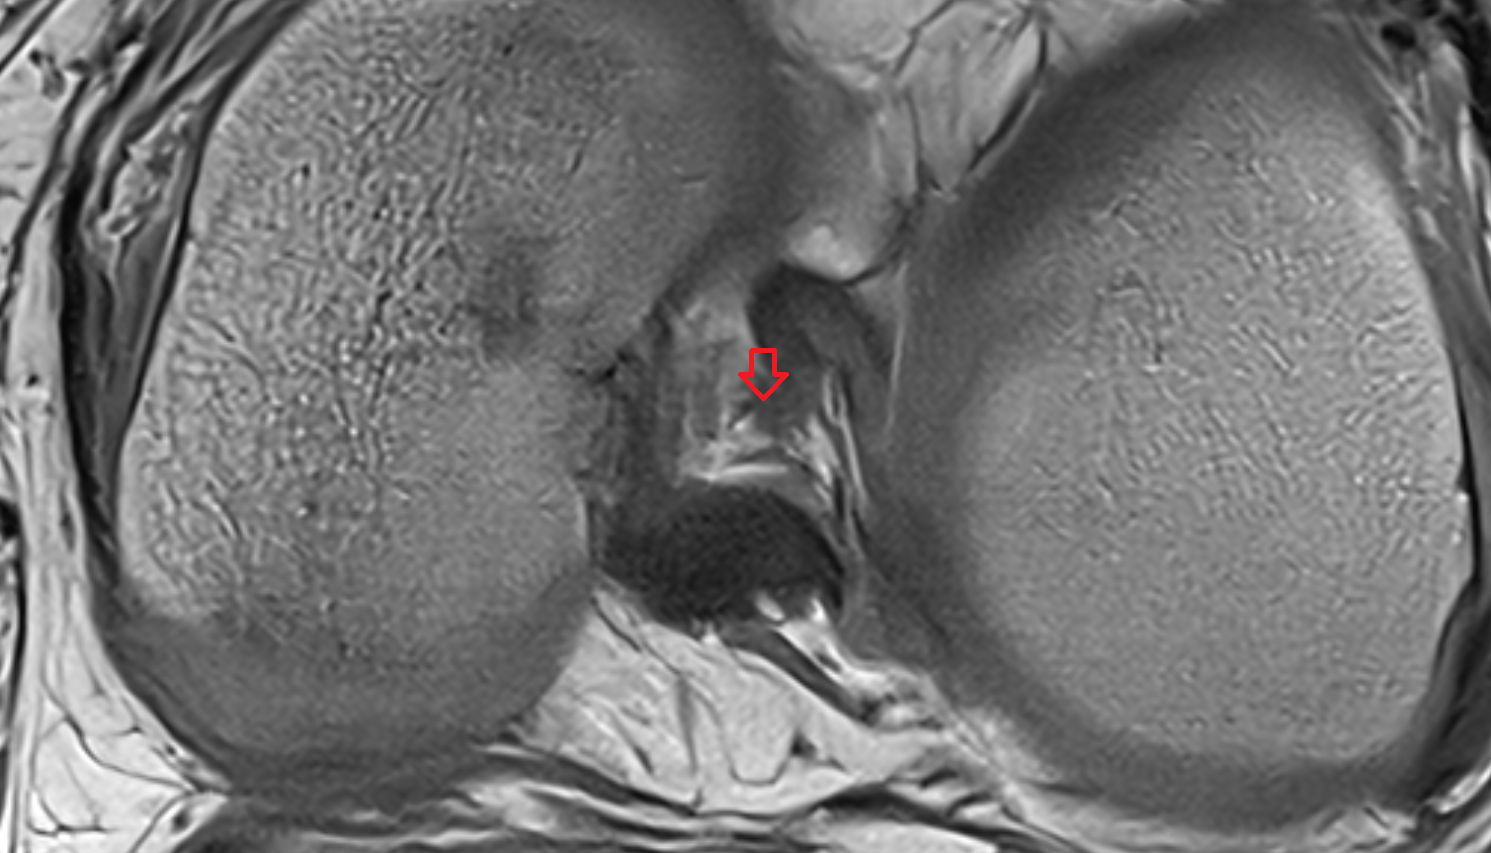

- Knee Joint